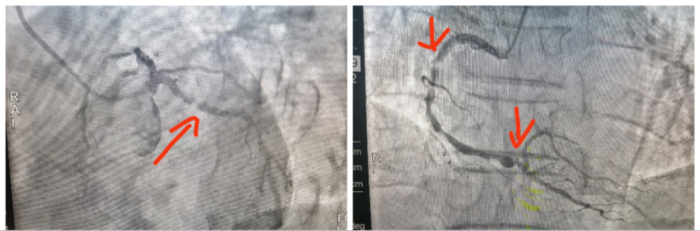

74岁的梁爷爷(化名)自述在一年前的一次检查中发现右肺上有一结节,为寻求解决慕名到中南大学湘雅二医院桂林医院临桂院区胸外科就诊。患者冠脉血管造影检查提示其冠脉多支多处狭窄,8月13日的冠脉造影检查结果提示,患者心脏冠状动脉三支血管病变——右冠脉、回旋支有弥漫性狭窄合并钙化,多处病变狭窄超过90%。

术前患者冠脉病变严重